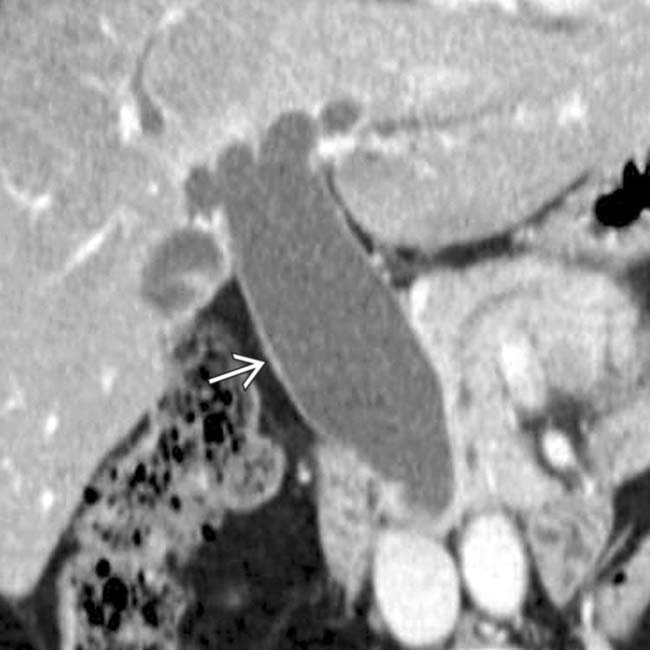

From www.researchgate.net

Choledochal cyst Type Ic a fusiform dilatation (arrow) in the common Type Ic Choledochal Cyst A choledochal cyst (cc) or biliary cyst is a congenital or acquired anomaly affecting the biliary tree. Type i cysts are a dilatation of the extrahepatic bile duct. Biliary cysts, also termed choledochal malformations, are cystic dilations that may occur singly or in multiples throughout. Choledochal cyst is a congenital cystic dilation of a part of bile duct that occurs. Type Ic Choledochal Cyst.